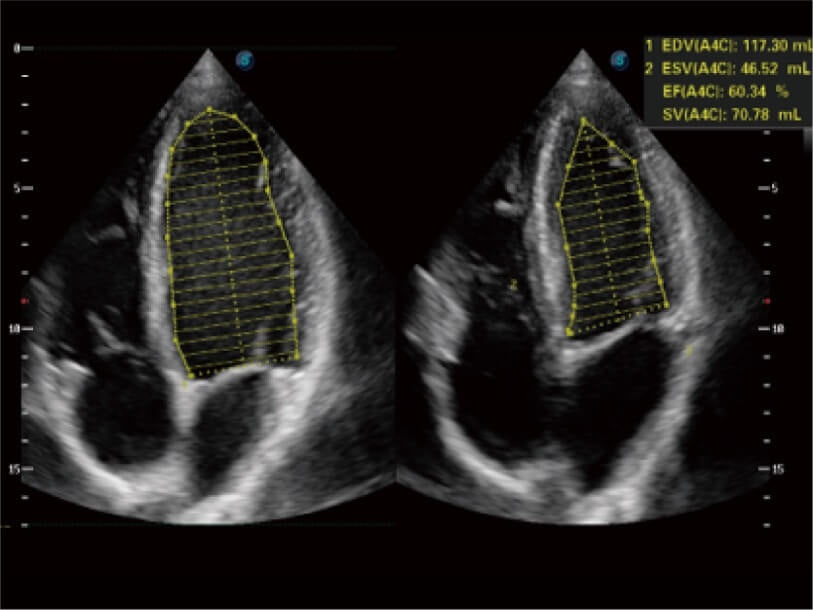

- Rendimiento superior: Imágenes excepcionales para abdomen, superficie y corazón.

- Herramientas cardíacas avanzadas: Evaluación completa de la función cardíaca.